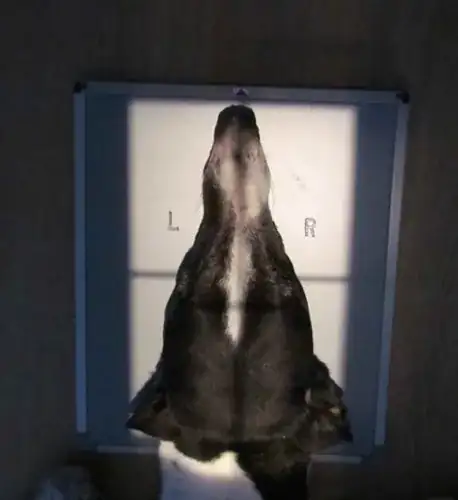

And here's an example of a canine head using the DorsoVentral positioning

and you can see that the image is not reversed which I presume is because this is the normal way to read these type of images.